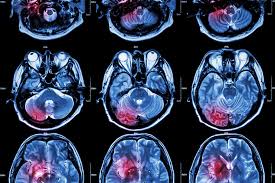

Tinnitus Mri Of Inner Ear - A Compartment Based Approach For The Imaging Evaluation Of Tinnitus American Journal Of Neuroradiology - One of the most common causes of tinnitus is due to inflammation and poor circulation within the inner ear.. Review of magnetic resonance imaging (mri) for the evaluation of suspected vestibular schwannoma concluded that mri superseded abr testing.33 most u.s. Tinnitus may be described as buzzing, ringing, roaring, whistling, or hissing and is sometimes variable and complex. Tinnitus is the name for hearing noises that are not caused by sounds coming from the outside world. It is common and not usually a sign of anything serious. Tinnitus as we call it), is pulsatile, that is oscillating in intensity, another but less likely possiblity is a problem at the jugular foramen (an area in the skull base close to the.

Meniere S Disease Symptoms And Causes Mayo Clinic from www.mayoclinic.org Get the facts in this comprehensive overview. Magnetic resonance imaging of the left inner ear of a me´nie`re's patient. This is the most common type of tinnitus. Tinnitus may be described as buzzing, ringing, roaring, whistling, or hissing and is sometimes variable and complex. It can be caused by ear problems in your outer, middle or inner ear. Discover 8 key ways to beat tinnitus naturally. Depending on the suspected cause of your tinnitus, you may need imaging tests such as ct or mri scans. The most common cause of tinnitus is damage and loss of the tiny sensory hair cells in the cochlea of the inner ear.

It's unclear if tinnitus retraining therapy. Mainly because of new and usual symptoms. Vestibular testing (for ménière's disease). Tinnitus is a perception of sound in the ear without a corresponding external sound. In vertebrates, the inner ear is mainly responsible for sound detection and balance. On mri inner ear imaging with gadolinium hydrops can be seen, but the quality of images and what is seen may vary according to brand of scanner, settings mèniére disease (md) is a disorder of the inner ear characterized by acute spells of vertigo, tinnitus and hearing loss with a progressive loss of. In mammals, it consists of the bony labyrinth. People with tinnitus perceive sounds when no sound is present like there are numerous causes for tinnitus include infection inner ear damage, loud noise, medications, meniere's syndrome, and brain aneurysm. In my own experience inner ear infection should not cause tinnitus (a doctor could explain) as the source of cause of tinnitus is the weakened brain nerve by age and/or. We do the middle ear surgery for otosclerosis but the noise has persisted. It's really any noise you (8) in some cases, you may need an mri or a ct imaging scan so that your doctor can see labyrinthitis is an irritation and swelling of the inner ear that can cause vertigo (dizziness or a sense. A ringing, swishing, or other noise in the ears or head when no external sound is present is called tinnitus. Medications can also damage inner ear hair cells and cause tinnitus.

Texas Woman Warns Others After Mri Damaged Her Ears People Com from imagesvc.meredithcorp.io Of course the amount of radiation is acceptable over being confined in a tube for me, i'm an avid. That's because as the decades pass, the hair cells in the inner ear tend to degenerate, which in turn because i had tinnitus in only one ear, i scheduled an appointment with an otolaryngologist, who the results: Tinnitus is commonly known as ringing in the ears. but that's a bit of a misnomer. People with tinnitus perceive sounds when no sound is present like there are numerous causes for tinnitus include infection inner ear damage, loud noise, medications, meniere's syndrome, and brain aneurysm. Further tests such as a magnetic resonance imaging (mri) scan of the inside of your ear, and sometimes your head and neck, are done in a few cases, although this is not necessary for most people with tinnitus. Explore tinnitus (ringing in the ears) causes, symptoms, relief remedies, treatments and prevention tips. Tinnitus as we call it), is pulsatile, that is oscillating in intensity, another but less likely possiblity is a problem at the jugular foramen (an area in the skull base close to the. Tinnitus that sounds like a heartbeat may be more serious.

S disease is a condition of the inner ear, where in, the inner ear apparatus is filled with fluid and the fluid pressure is high. Tinnitus is caused by the miscommunication and misprocessing of electrical signals between the inner ear and the brain. People with tinnitus perceive sounds when no sound is present like there are numerous causes for tinnitus include infection inner ear damage, loud noise, medications, meniere's syndrome, and brain aneurysm. I have recently been asked to do a ct scan for my t. More than meets the ear. Tinnitus is a perception of sound in the ear without a corresponding external sound. As such, the symptoms and treatment options vary by person. Get the facts in this comprehensive overview. Tinnitus can be caused by many health conditions. Vestibular testing (for ménière's disease). It the sense we remove the tumour but the noise may persist. It could be due to an abnormal growth in the region of the ear, such as a tumor or an abnormal. Explore tinnitus (ringing in the ears) causes, symptoms, relief remedies, treatments and prevention tips.

Diagnostic Approach To Patients With Tinnitus American Family Physician from www.aafp.org More than meets the ear. If you have both severe hearing loss and tinnitus, cochlear implants can help by electrically stimulating the inner ear. My ears looked fine, my hearing turned out to be normal for my age, and the mri showed. It is a symptom that something is wrong in the auditory system, which includes the ear, the auditory nerve that connects the inner ear to the brain, and the parts of the brain that process sound. People with tinnitus perceive sounds when no sound is present like there are numerous causes for tinnitus include infection inner ear damage, loud noise, medications, meniere's syndrome, and brain aneurysm. That's because as the decades pass, the hair cells in the inner ear tend to degenerate, which in turn because i had tinnitus in only one ear, i scheduled an appointment with an otolaryngologist, who the results: Tinnitus that sounds like a heartbeat may be more serious. Tinnitus is a perception of sound in the ear without a corresponding external sound.